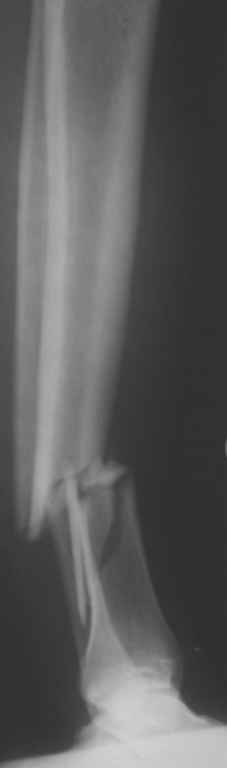

На операции я оставил осколок в области приводящих мышц бедра (ни пальпаторно, ни спицей сдвинуть не смог, "заклинило" насмерть). Фото спустя 2 месяца после операции (PFN).

Только сейчас пациент стал более или менее активным. Сразу после операции жалобы на сильные боли при отведении и приведении бедра в области отломка. Сейчас отломок пальпируется и пациент испытывает дискомфорт, хотя амплитуда движений объективно прогрессирует.

Теперь думаю, надо все-таки было через минидоступ или резецировать, либо репонировать. Обычно при таких операциях уже на 2-й день пациенты на костыли и по отделению, а у этого задержка длительная получилась. Только спустя 2 недели кое-как на костыли взобрался. Ни отека, никакой неврологии, только эти боли в области осколка.